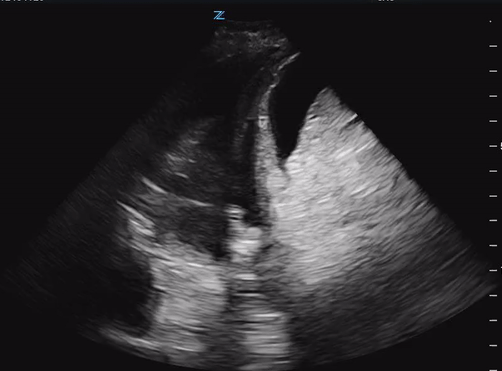

You start the patient on 2L NC with improvement in her oxygenation. While your nurse is getting an IV, you complete a RUSH exam to help figure out why the patient is hypotensive. Your cardiac views shos grossly normal EF, no pericardial effusion, collapsible IVC. RUQ view below:

A second example of hepatic hydrothorax, again with fluid above and below the diaphragm in the context of a nodular appearing liver.

Cirrhosis is characterized by hepatocellular necrosis leading to fibrosis, nodular regeneration and distortion of hepatic architecture which can be identified on ultrasound by:

- nodular or bumpy appearing liver edge

- hypoechoic nodules seen within the parenchyma

- overall coarse, heterogenous appearance

- may have signs of portal hypertension (distended portal vein)

- may also have ascites and splenomegaly